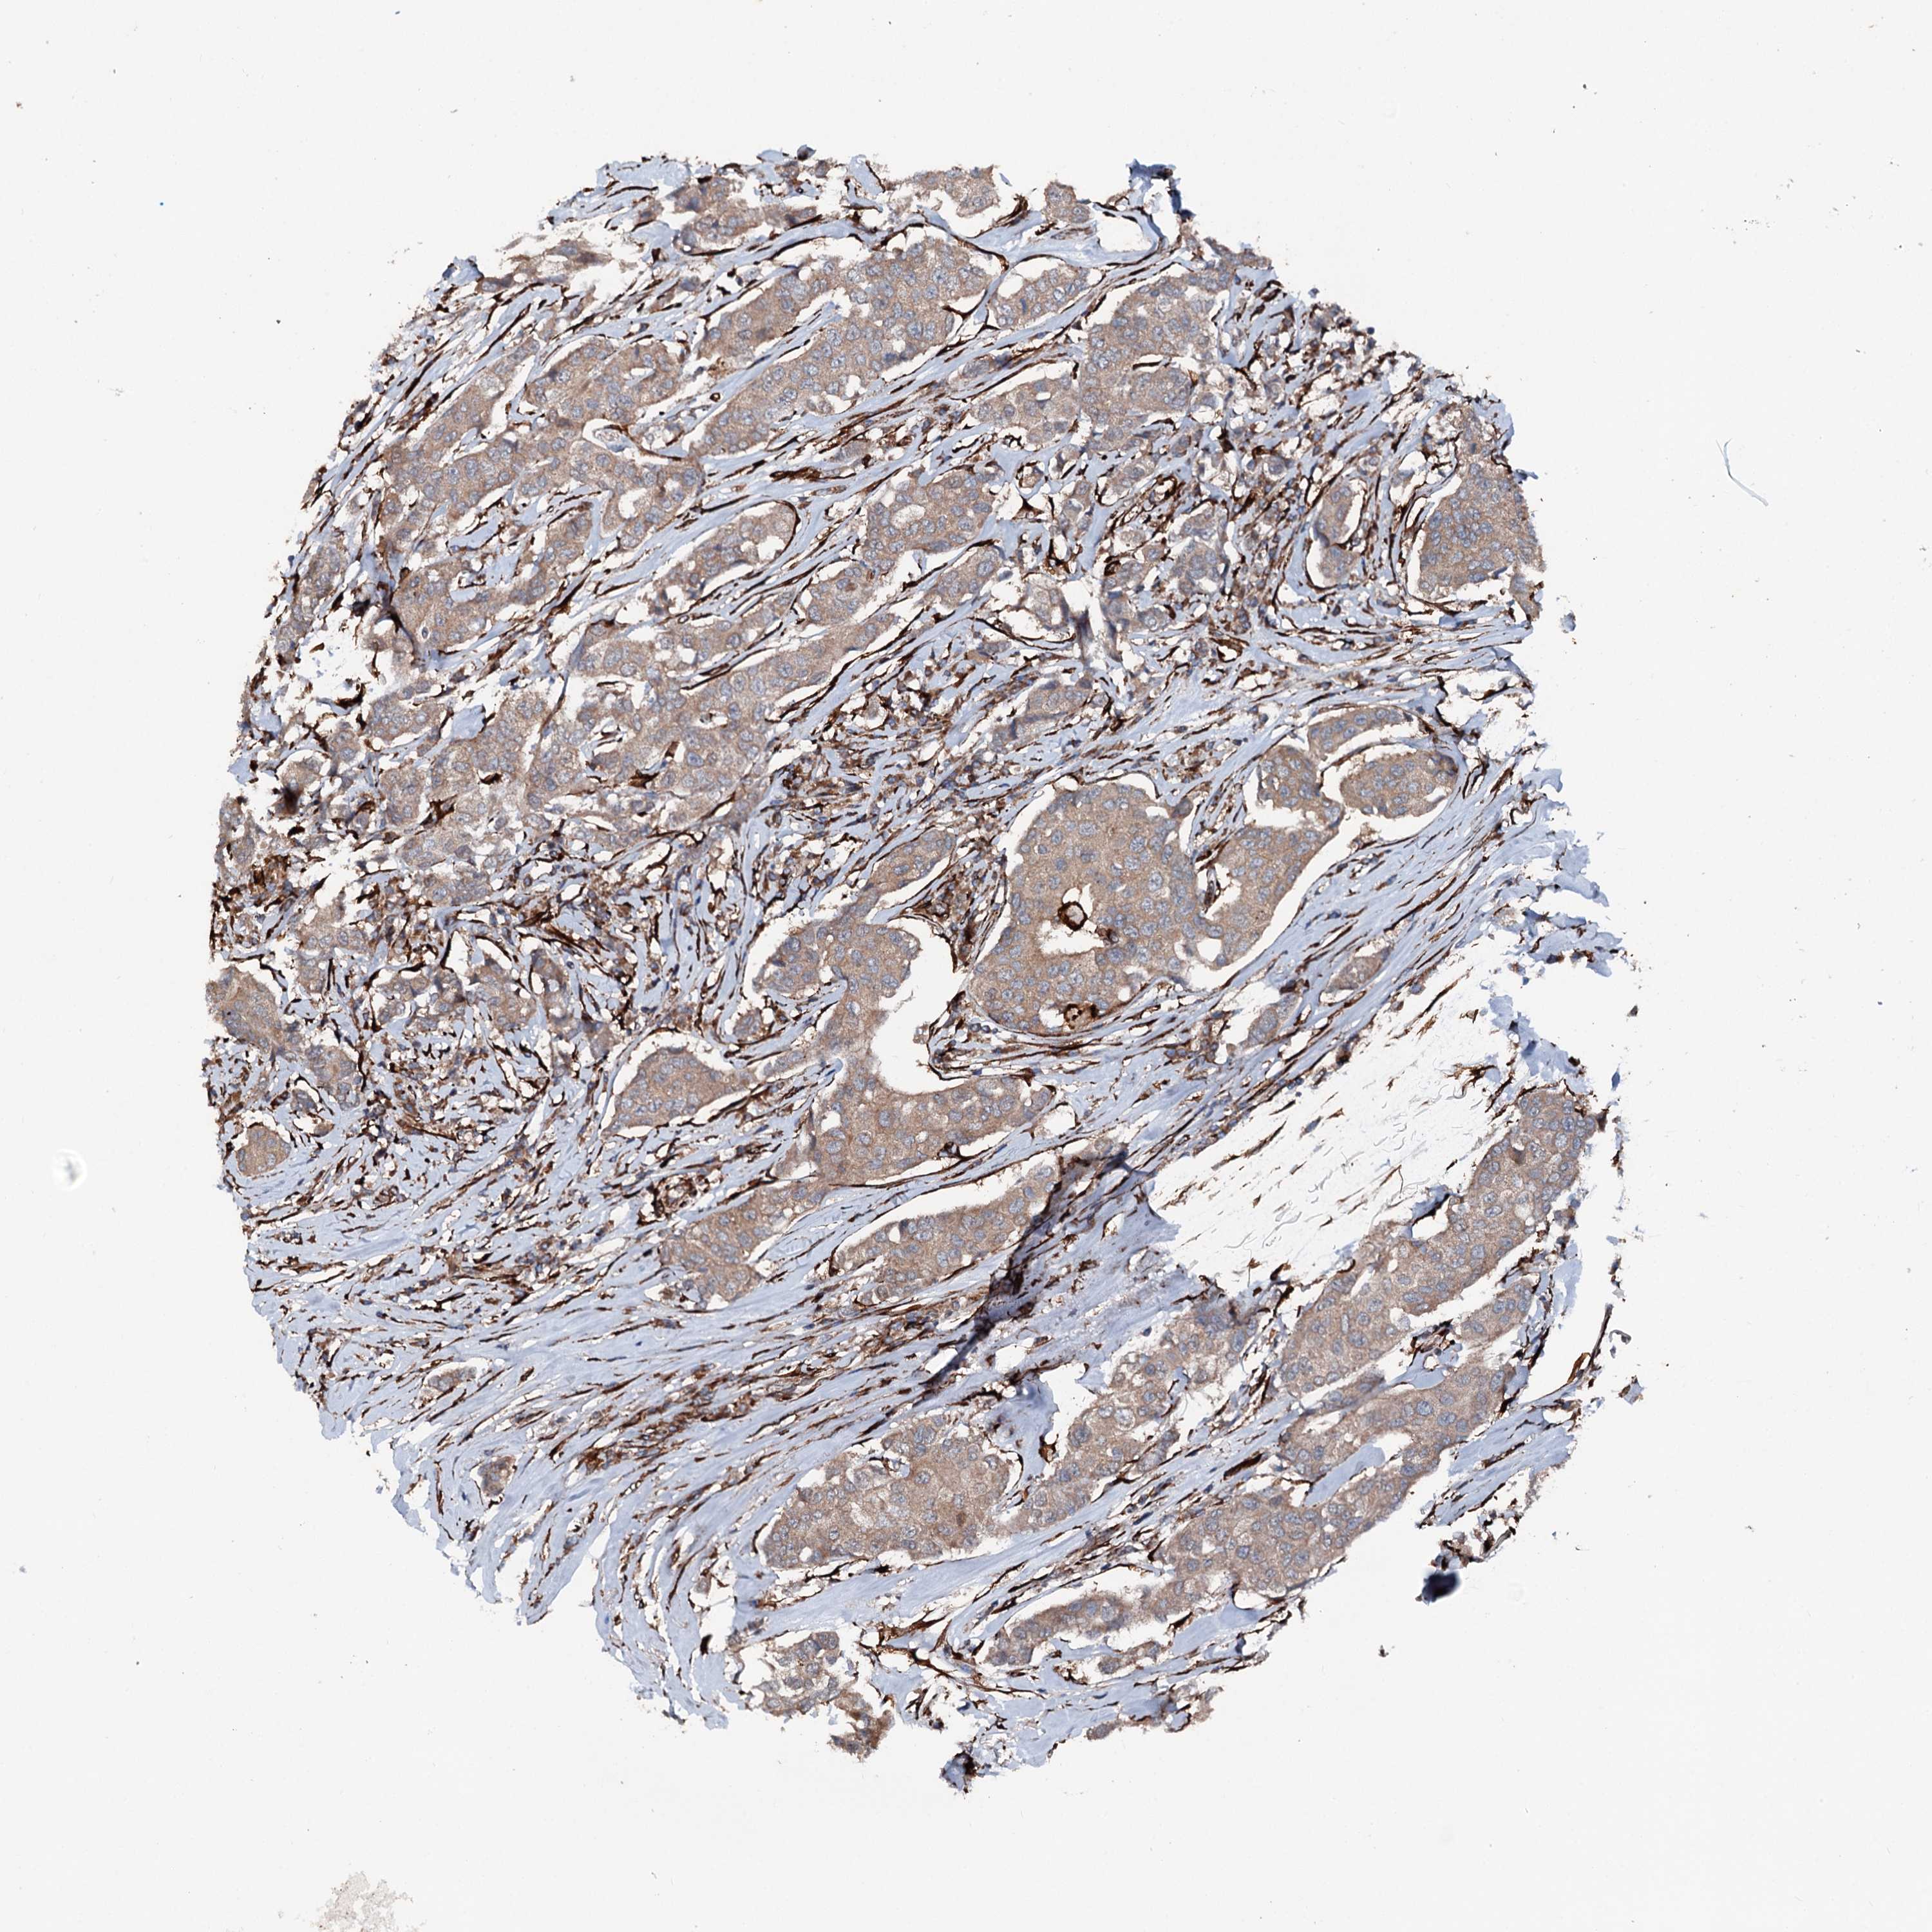

CANCER BREAST CANCER Show tissue menu

BRCA TCGA BRCA VALIDATION PROTEIN EXPRESSION